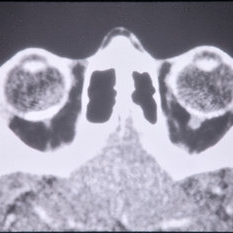

CT Scan of Brain Showing Cerebral Hypoplasia

CT Scan of Brain Showing Cerebral Hypoplasia

Feb 20 2015 by H. Michael Lambert, MD

CT scan of brain showing cerebral hypoplasia

Condition/keywords: cerebral hypoplasia, CT scan, linear nevus sebaceous syndrome